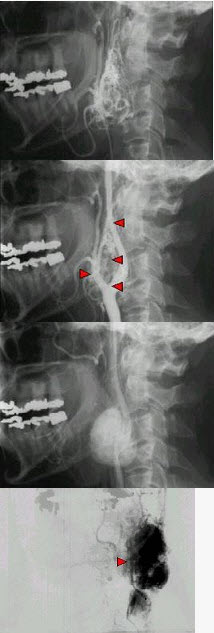

50岁女性,颈部无痛性肿块,逐渐增大,听诊可闻及杂音,DSA检查如图所示,请选择最可能诊断()。

A、颈动脉体瘤

B、假性动脉瘤

C、颈动脉夹层

D、颈动脉硬化

E、动静脉瘘

正确答案:

A